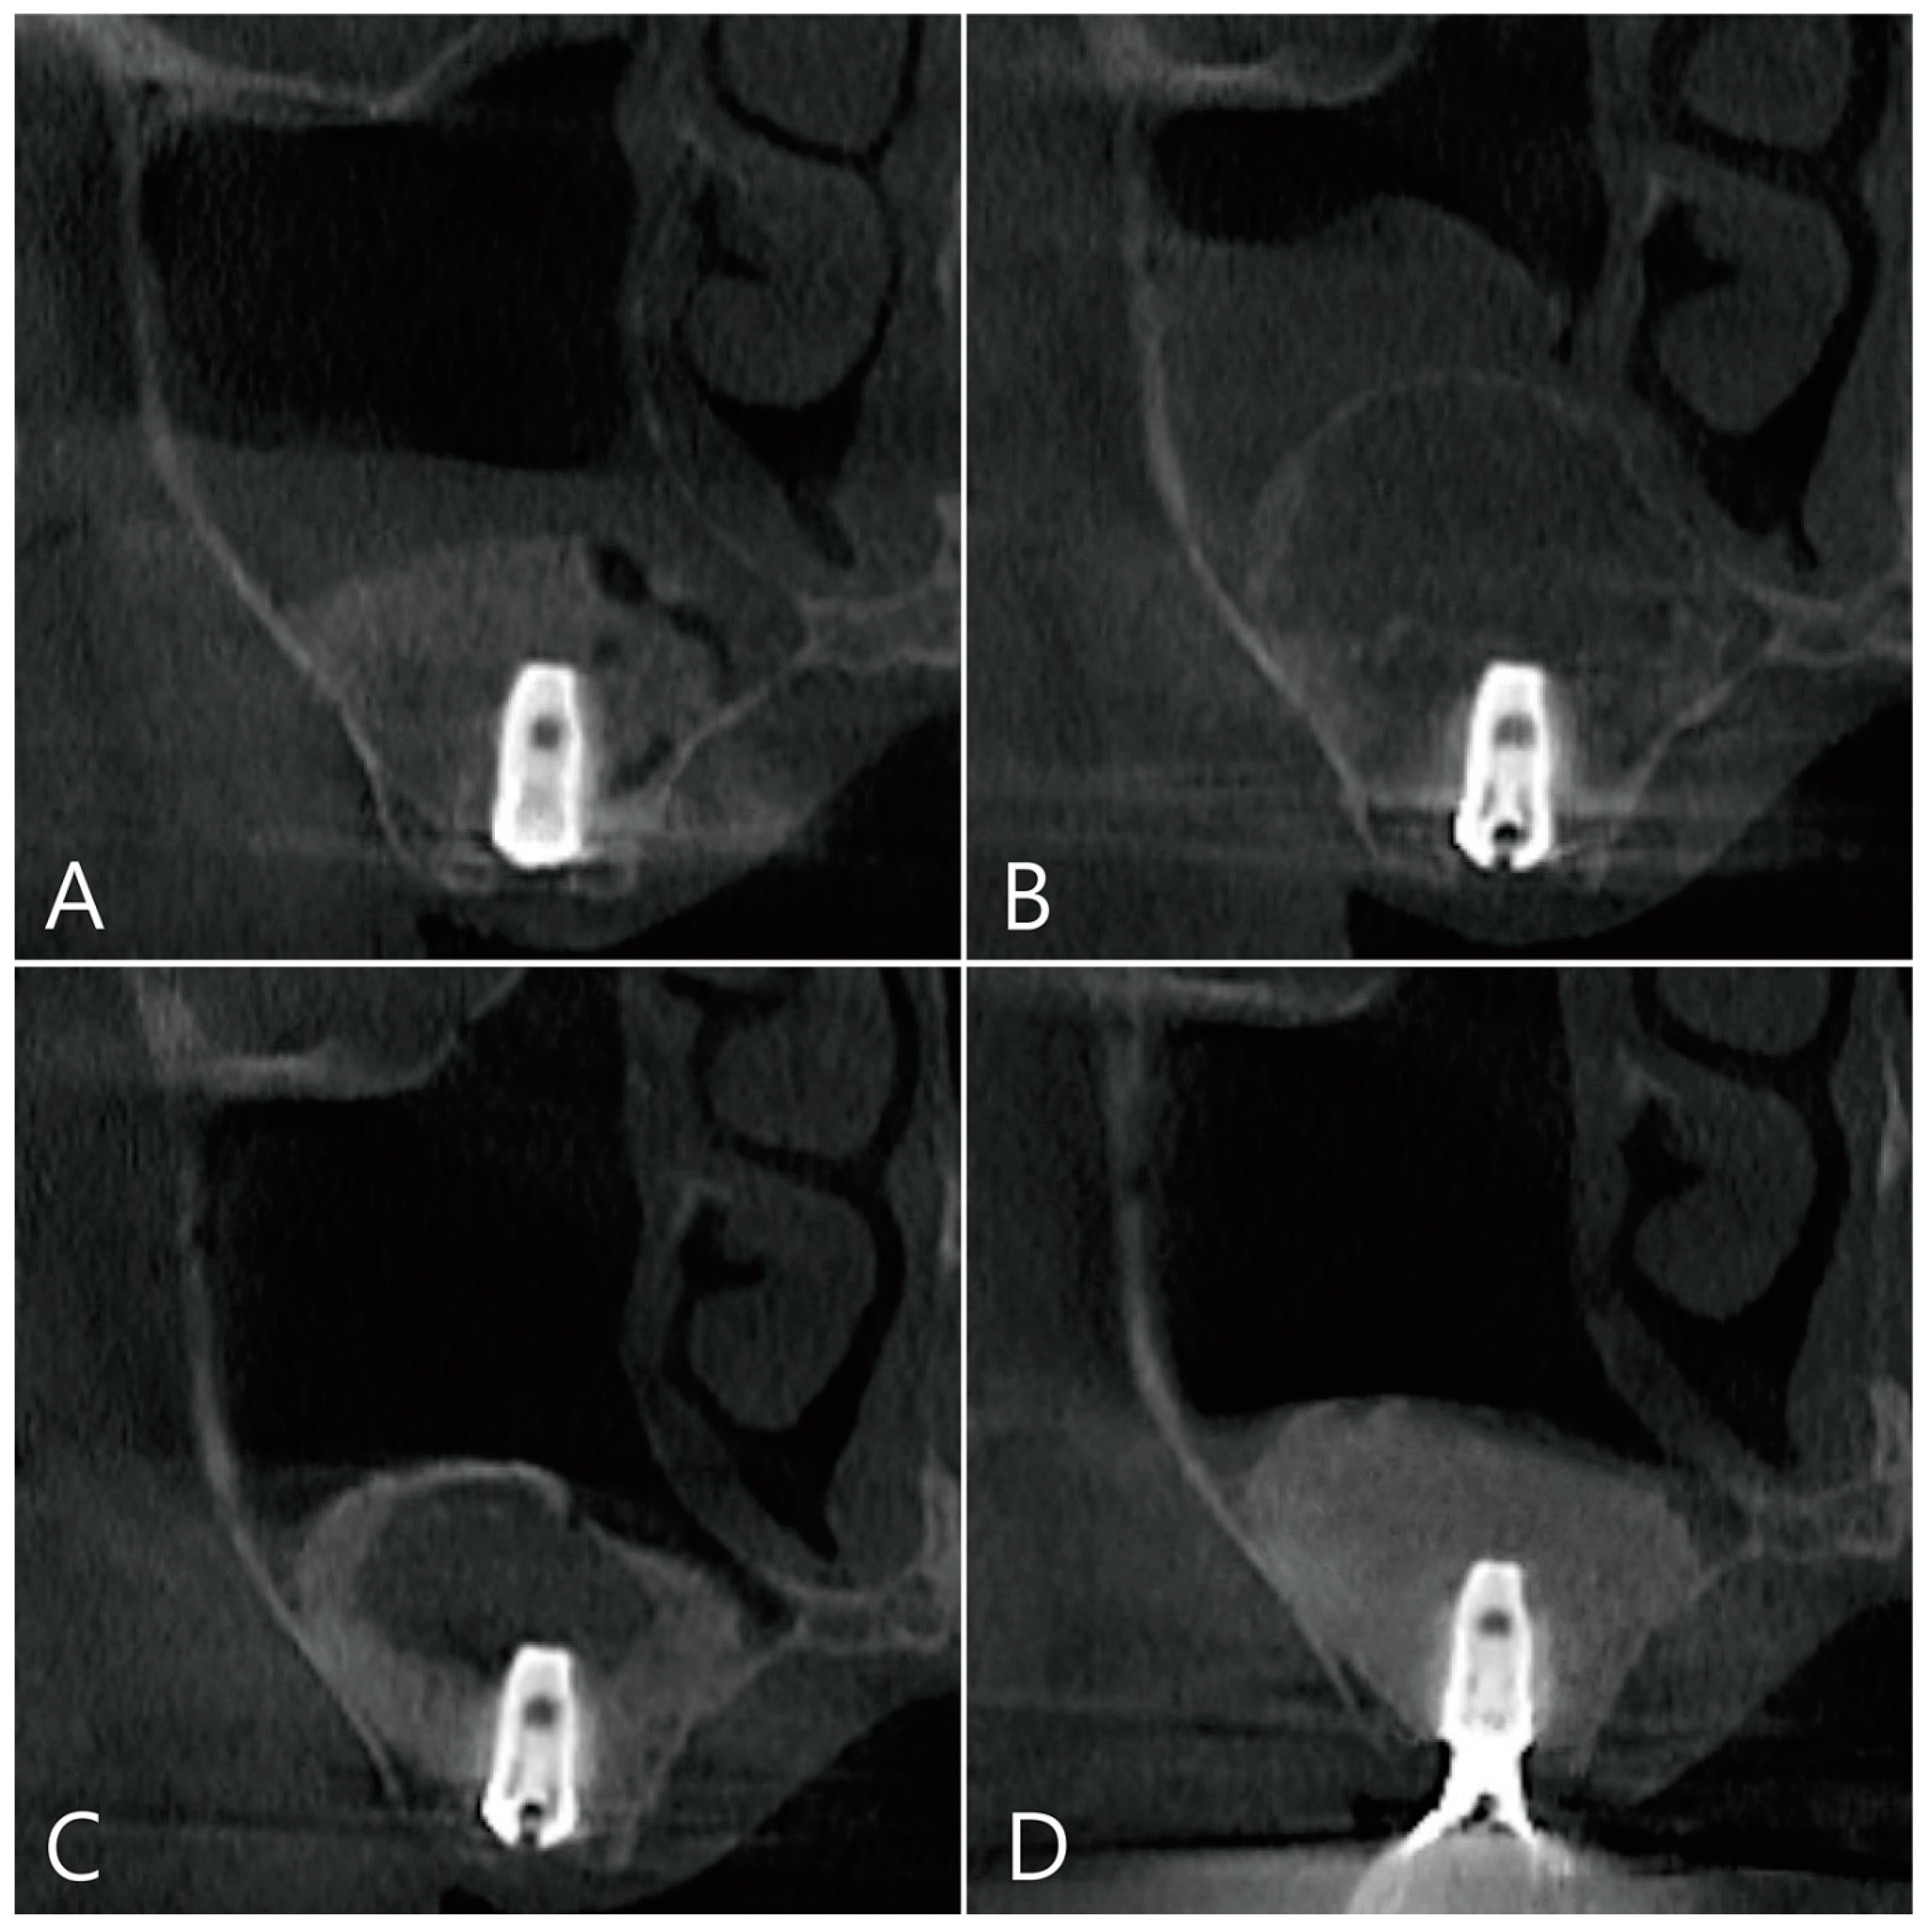

The coronal images of CBCT taken during the healing process after surgery were examined. There was no leakage of bone graft particles in the CBCT taken immediately after surgery (Figure 7A). One week after surgery, a large grafting void was developed over the apical third of the implant, and thickening of the sinus membrane was observed (Figure 7B). The shape of the grafting void after 6 months of surgery became clear and the size decreased. The sinus membrane thickening was also reduced. The void was filled with homogenous contents and showed a cystic appearance (Figure 7C). In the CBCT taken 6 months after the prosthesis was delivered, the bone graft substitute filled the grafting void well (Figure 7D).

Figure 7. Coronal images of the CBCT were taken at multiple points during the healing process after surgery: (A) an image taken immediately after surgery; (B) an image taken one week after surgery. A large grafting void occurred over the apical half of the implant, and thickening of the maxillary sinus mucosa was also observed; (C) in the image 6 months after surgery, the size of the grafting void was slightly reduced. The void presents with a cystic appearance resembling SCC. The apical bony support of the implant was lost. The grafting void was removed and additional bone grafting was performed; (D) in the CBCT image taken 6 months after the prosthesis was delivered, it can be confirmed that the previous grafting void was replaced with a bone graft substitute.